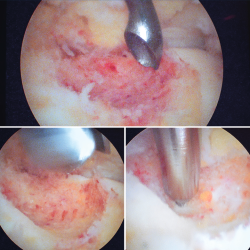

Posteriormente se realiza curetaje del fondo, eliminando el hueso sobrante en los márgenes, hasta encontrarnos hueso esponjoso de aspecto macroscópico normal, y se realizan perforaciones mediante NanoFx® (Arthrosurface Inc., Bellingham, Massachusetts) (Figura 6).

Figura 6. Curetaje del fondo de la lesión, visualizando hueso esponjoso de aspecto macroscópico normal. Finalmente se realizan nanoperforaciones.